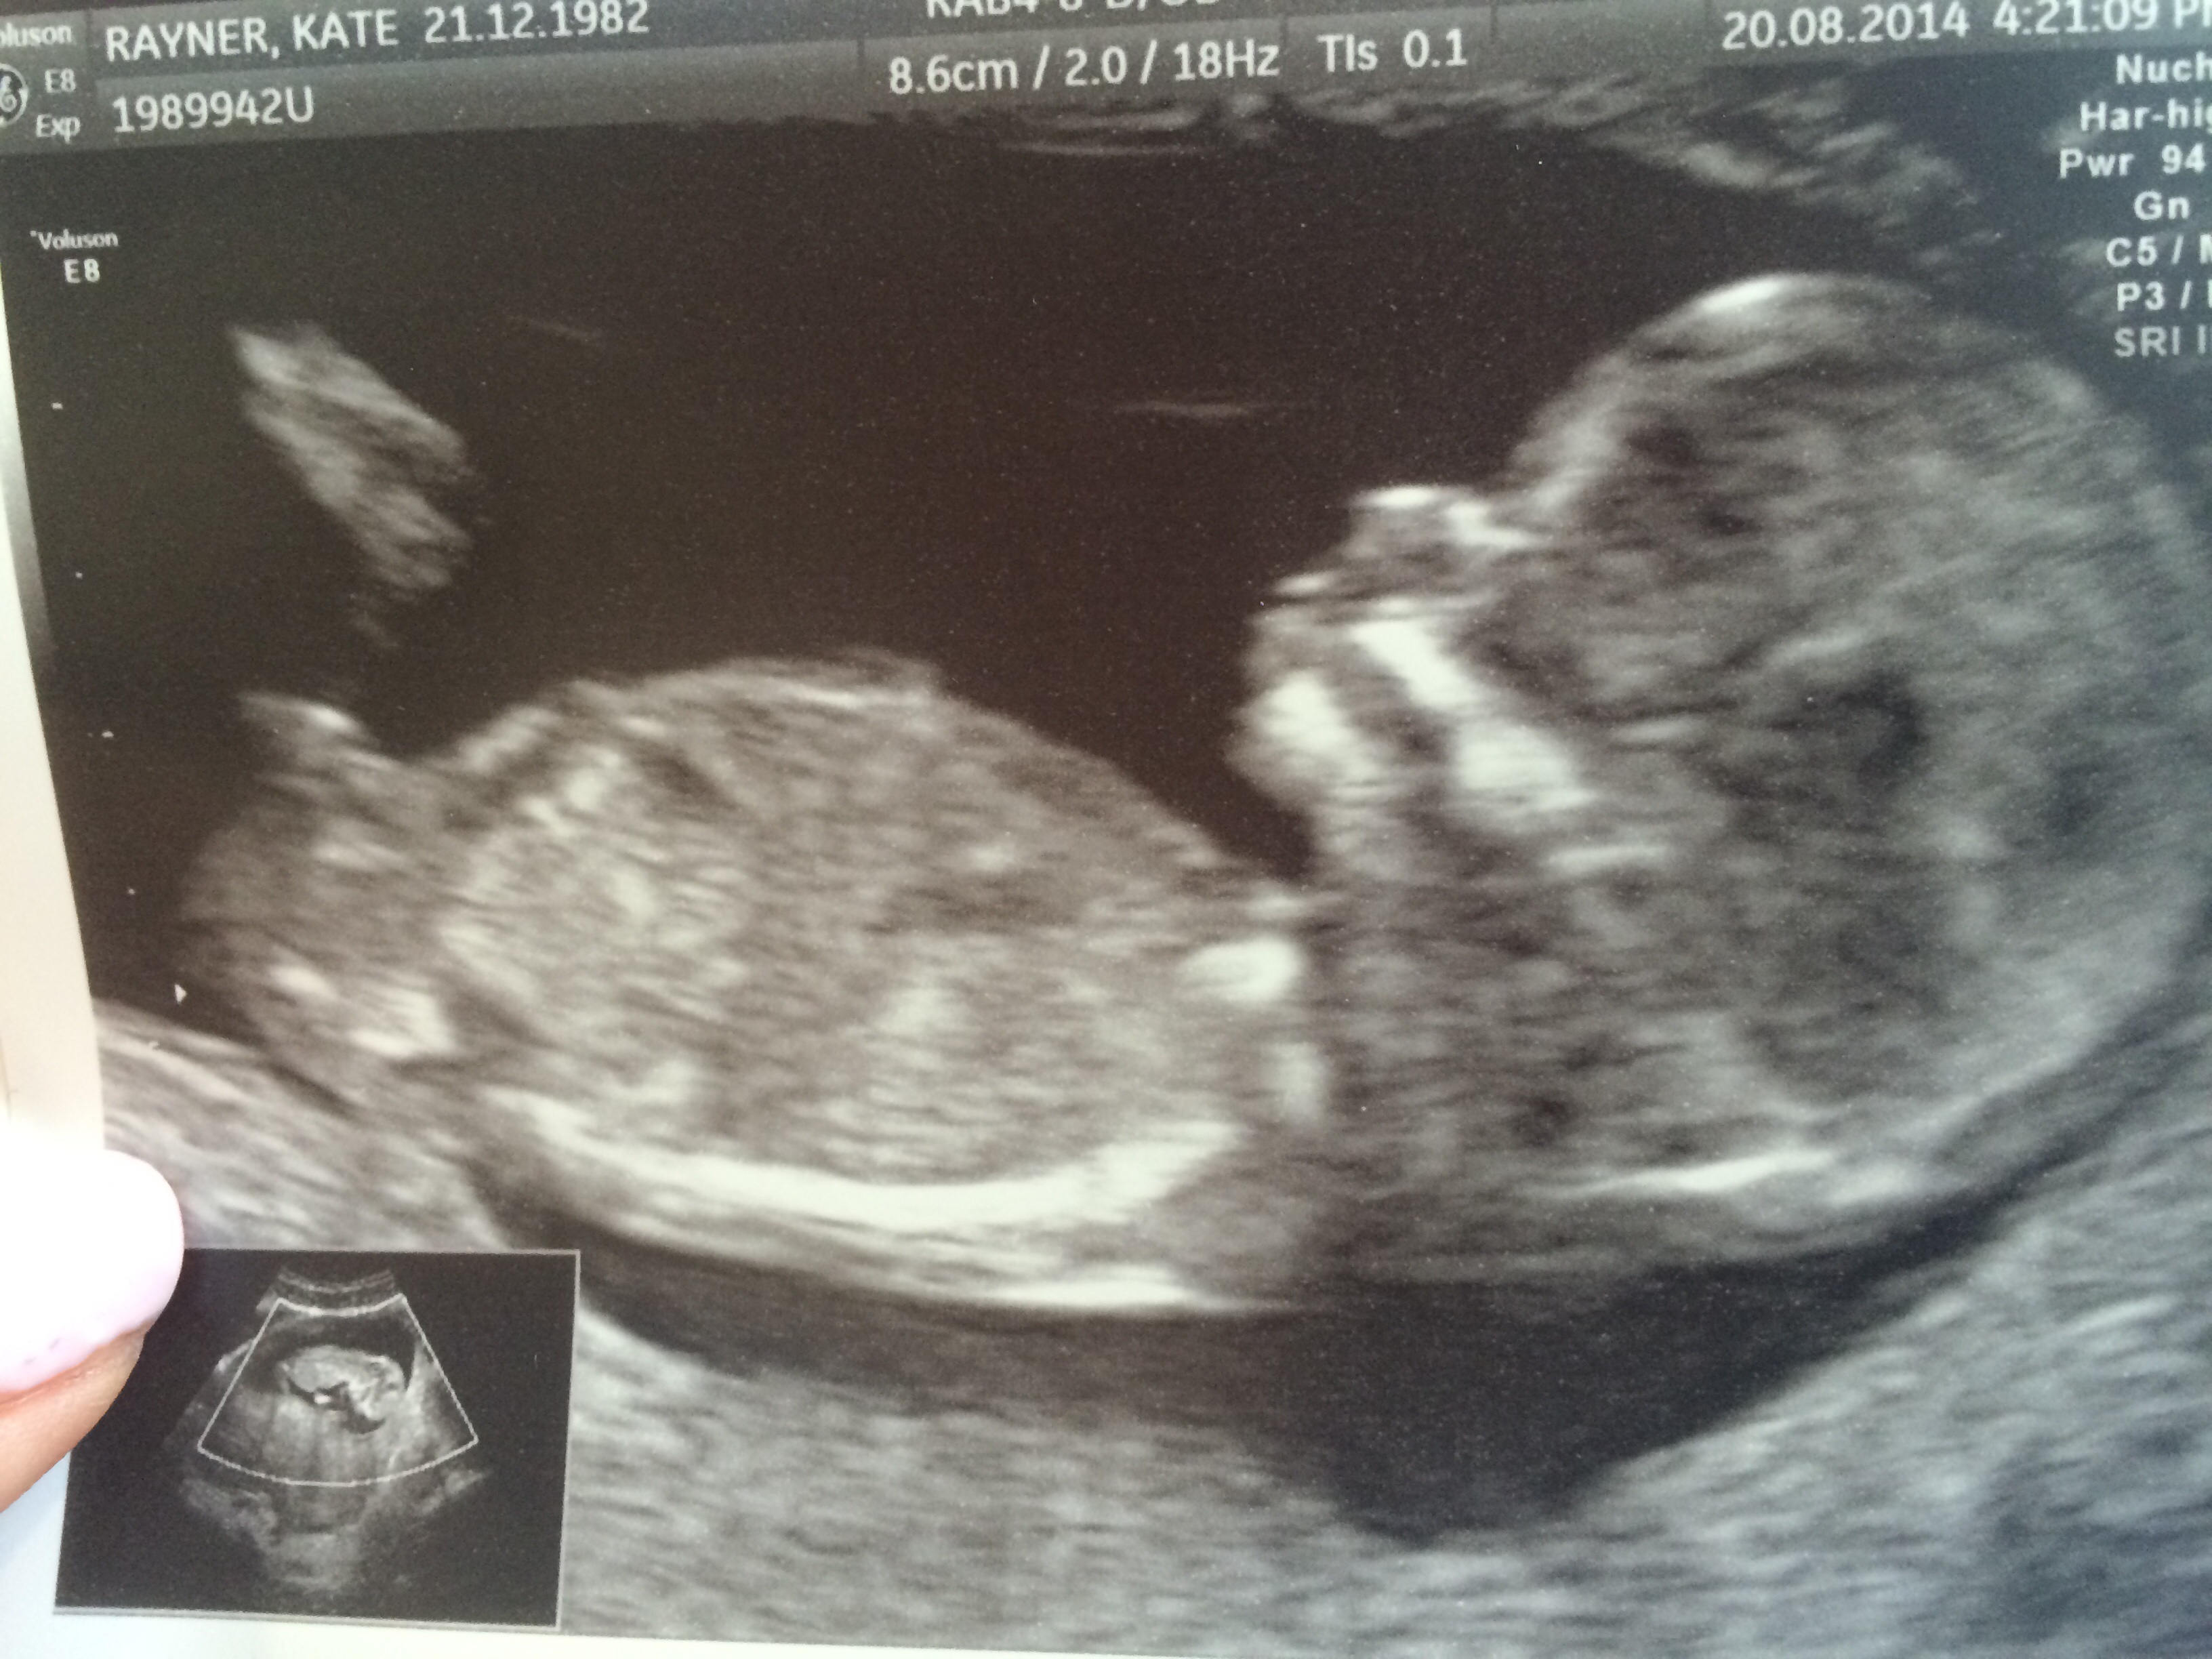

I can't decide if this is angled or not because of the curve in base of baby spine? Please help

Yeah, it looks more like a boy to me as well, but it could be thrown off because of the curved spine. Does look a little stacked though, which I believe is almost always boy, whereas forked is girl.

Yes that's what has thrown me off as I would have said boy straight away but someone else pointed out curved spine and said it looked almost horizontal. The head is very different to my boy and I've felt so different this time round! Is it not a bit big for a winkie? It looks huge... I thought it was a leg! Ha!

Does the fact that baby is upside down affect the nub theory?